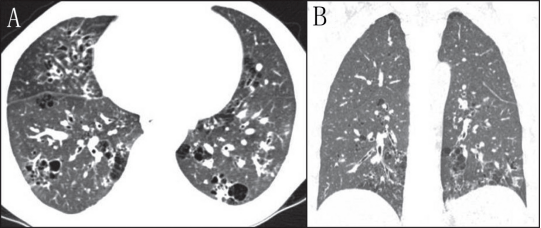

滤泡性细支气管炎(FB)也是累及肺的淋巴增生性疾病谱系的一种,与LIP主要区别为细支气管中心淋巴细胞浸润,不浸润到肺间质;此外,滤泡性毛细支气管炎最常见的表现形式是气道阻塞引起的空气潴留(11)。囊肿形成的主要机制是外部压迫支气管相关的淋巴组织,引起活瓣现象,但也可能与血管阻塞引起的细支气管缺血有关。这些囊肿与LIP囊肿相似,主要分布在支气管血管周围,薄壁(图4),也可以出现小叶中心结节或磨玻璃影。

4 女性滤泡细支气管炎患者的CT图像弥漫分布各种大小的薄壁囊肿,特别是沿支气管血管束周围的囊肿